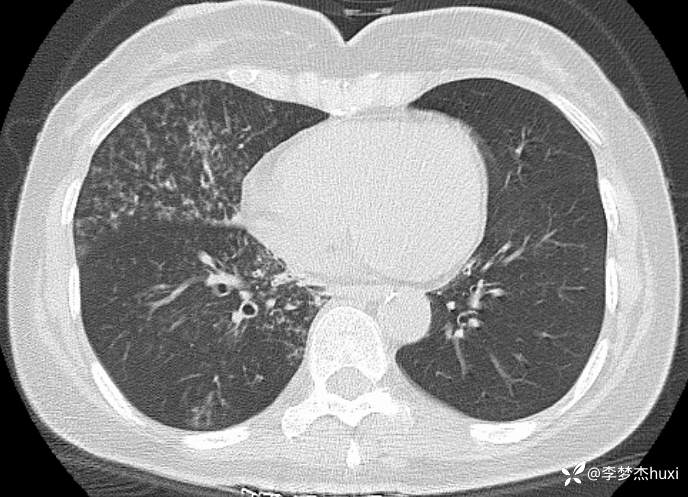

女性53岁,腮腺癌术后反复咳嗽、咳痰,胸部CT以树芽征为特点改变,最可能的是哪种疾病

【现病史及既往史】: 1.患者中年 女,患者于入院前5天无明显诱因出现咳嗽,咳痰,为黄绿色痰,量少,不易咳出,伴发热,最高体温不详,伴周身乏力,无胸痛,无呼吸困难,无恶心、呕吐,无腹痛、腹泻,无抽搐及意识障碍,院外未诊治,症状无好转,今患者及家属为进一步诊治前来我院就诊,门诊查胸部CT:右肺上叶占位性病变应考虑,右肺上叶空洞;右肺下叶占位?双肺炎症,支气管炎?右肺门淋巴结增大,双肺实性结节,纵隔结节,主动脉及冠状动脉钙化,右侧乳腺结节?建议结合超声,建议结合临床复查。门诊以“肺炎”收入院 。

2.既往高血压病史20余年,最高达180/?mmHg,目前口服“缬沙坦胶囊、硝苯地平控释片、酒石酸美托洛尔”等药物治疗,血压未监测;2008年因右侧腮腺腺样囊性癌于天津肿瘤医院行手术治疗,术后给予放化疗,2019年肿瘤原位复发,于北京大学口腔医院再次行手术治疗,2023-8发现肿瘤侵犯右耳道,目前口服仑伐替尼治疗约12个月;2023-11开始应用帕博利珠单抗注射液免疫治疗,患者右肺上叶占位,2024-7于沧州市中心医院行穿刺活检,病理:腺样囊性癌,2024-08于北京市某医院行“肺部射频消融术”;患者术后时常呛咳,否认“冠心病、糖尿病”病史,否认“肝炎”、“结核”等传染病史;否认外伤史,无输血史;否认食物、药物过敏史,预防接种史不详,系统回顾无特殊。。